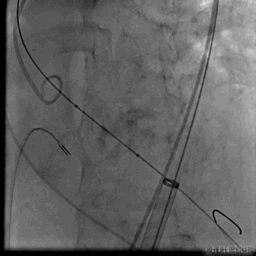

Numed18预扩

VenusA26定位